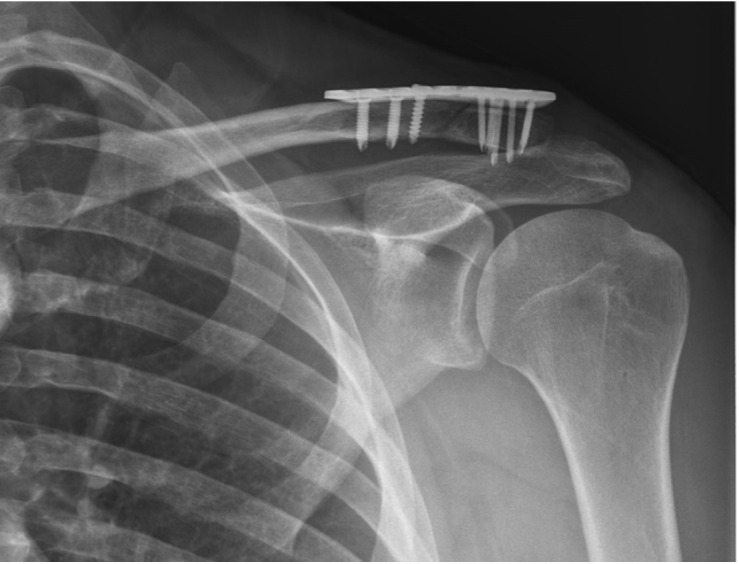

背景:喙锁韧带完整性受损的锁骨远端骨折不稳定会造成严重的不愈合风险,需要手术干预。尽管对于不稳定的锁骨远端骨折需要手术治疗的观点是一致的,但各种手术技术是可用的。本研究的目的是评估使用缝线内扣技术对2b型锁骨骨折进行CC增强的放射学和功能结果。方法:本回顾性研究将42例符合标准的患者分为两组:1组(锁定钢板加CC强化)和2组(锁定钢板不加CC强化)。记录随访期间的人口统计数据、Constant-Murley评分(CMS)、愈合时间、活动范围、并发症和种植体失败情况。结果:女性13例(31.0%),男性29例(69.0%)。平均年龄40.5±11.5岁。合并时间(周)(t(40)=-2.11, P=0.04)和6月CMS (t(40)=4.19, P=0.01)差异有统计学意义。两组术后并发症比较差异无统计学意义(P < 0.05)。结论:在2b型锁骨远端骨折的CC增强术中采用缝合内扣可获得较好的短期功能和影像学结果。证据水平:III。

Background: Instability in distal clavicle fractures with impaired integrity of the coracoclavicular (CC) ligament poses a serious risk of nonunion, necessitating surgical intervention. Despite a consensus on the need for surgery in cases of unstable distal clavicle fractures, various surgical techniques are available. The aim of this study is to evaluate the radiological and functional outcomes of CC augmentation using the suture Endobutton technique for Neer type 2b clavicle fractures were evaluated.

Conclusions: CC augmentation with a suture Endobutton in type 2b distal clavicle fractures resulted in more favorable short-term functional and radiological outcomes. Level of evidence: III.